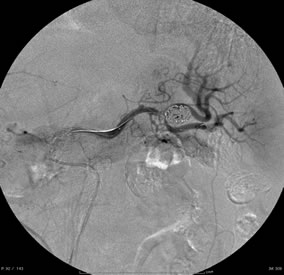

血管造影検査を用いた肝細胞癌に対する肝動脈化学塞栓療法。

カテーテルを腫瘍濃染の近くまで進めて塞栓しています。

内臓動脈瘤への経皮的塞栓術

脾門部の動脈瘤に対して塞栓用コイルにて塞栓術を施行しています。